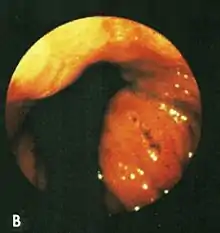

Red, congested folds with blood on a Cameron lesion.

After aspirating some air through the endoscope, this lesion was seen rubbing against opposite folds at the diaphragm level on respiration.

Based on their surgical observations, Windsor and Collis in 1967[4] proposed that blood loss was due to local trauma to the stomach where it rides to and fro in the hiatus on respiration. Boutelier et al.[8] noted on gastroscopy ulcers and erosions at the level of the neck of the hernia in individuals with acute and chronic bleeding, but no detailed description was given. Cameron and Higgins in 1986[1] described linear gastric erosions, later called "Cameron lesions", in people with x-rays showing one-third or more of the stomach above the diaphragm.[9][10][11][12][13][14][15] (figure 1). Over 6 years, Cameron and Higgins studied 109 persons with large hiatal hernias, 55 with anemia and 54 without anemia, at esophagogastroduodenoscopy. Cameron lesions, often multiple, were found at or near the level where the herniated stomach was constricted by the diaphragm. The lesions were typically white, superficial, linear, and oriented along the crests of inflamed appearing mucosal folds (figure 2). Small amounts of blood were often seen on the lesions (Fig 3). Mucosal folds at the diaphragm level were often seen rubbing against each other on respiration (Fig 4). It was proposed that the lesions were caused by mechanical trauma at the level of constriction by the diaphragm [1] Cameron lesions were found in 42% of persons with anemia compared to 24% in those without anemia, a statistically significant difference, p<0.05. Spots of fresh or clotted blood were seen on the lesions in 25% of persons with anemia compared to 7% without anemia, also a significant difference, p<0.05. In the 109 persons in this study, 15 had reflux esophagitis, 11 had peptic ulcers, and 7 had Barrett's esophagus, but none of these findings correlated with anemia. Thus, in people with large hernias, Cameron lesions with evidence of slow bleeding were associated with iron deficiency anemia.